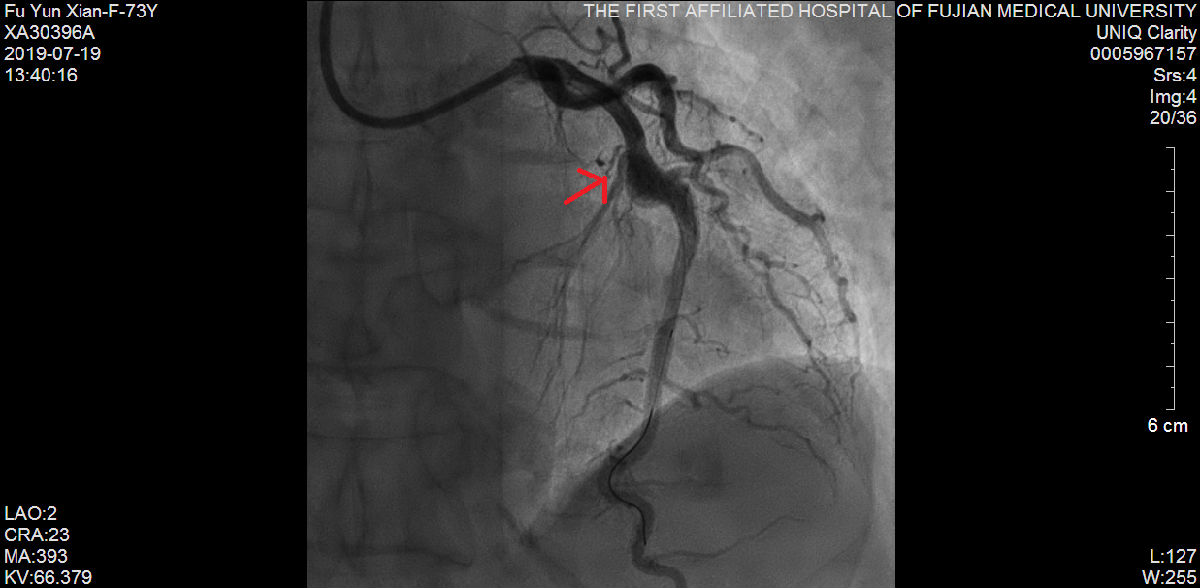

随后,苏津自教授、蔡瀚医师为傅阿姨进行介入手术:肾动脉造影显示双侧肾脏萎缩,右侧肾脏具备进行RDN的条件;而冠状动脉造影显示营养心脏的其中一条主干血管——前降支血管近端99%狭窄伴冠状动脉瘤样扩张。

说干就干,要干就干的漂亮。苏津自团队立即为傅阿姨进行RDN。经过术后3周细致入微的诊疗和护理,傅阿姨血压慢慢下降至160/90mmHg左右,体重也增加到40公斤。随后,柴大军教授、祝江医师在冠状动脉血管内超声(IVUS)的精确定位下,成功为傅阿姨植入一枚支架至前降支血管。前后历经1个月,傅阿姨再也没感觉头痛、胸痛,笑着出院了。